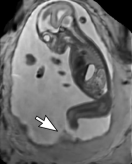

During image acquisition the fetus is not sedated and moves freely as well as the mother breathes normally. As a result, movements are likely to corrupt the scans, hiding pathology and causing overlap between different anatomical regions. In order to limit these artifacts, fast scanning sequences such as ssFSE [10] allow for the rapid acquisition of single slices at high in-plane resolution in a large field of view and good tissue contrast of the uterus. However, when acquiring a 3D volume through a stack of slices, inter-slice artifacts in the out-of-plane views are highly likely. Consequently, this restricts reliable diagnostics to individual slices in the current clinical practice. Fig. 1 depicts a typical example of motion related artifacts in a fetal single-shot fast spin echo (ssFSE) scan. The observed motion (c.f. Fig. 1 b & c) is of unpredictable nature and consists of a combination of maternal respiration movements, fetal movements and bowel movements.

Reconstruction of Fetal Organs: Exemplary PVR and SVR reconstructions under motion introduced by kicking of the fetus are shown in Fig. 11. PVR reconstruction results show an improved visual appearance and less blurring in the region with severe motion artifacts (arrow). An example of a challenging clinical case with a kidney malformation in one of twin fetuses, is shown in Fig. 8. Our clinical partners confirmed that such complications are easier to examine and to quantify after PVR-based reconstruction.